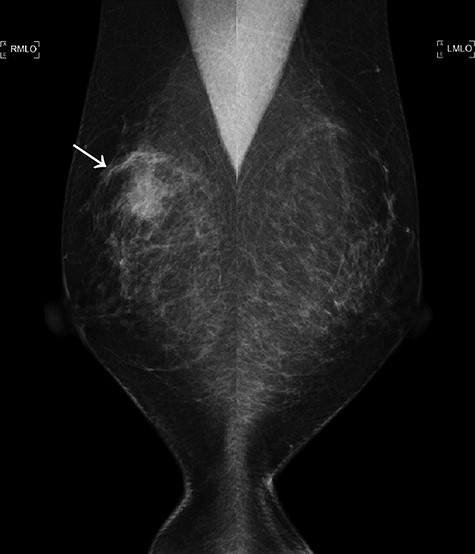

The first mammogram. The mammogram displaying a highly dense micro-serrated mass in the right upper lateral region (arrowhead).